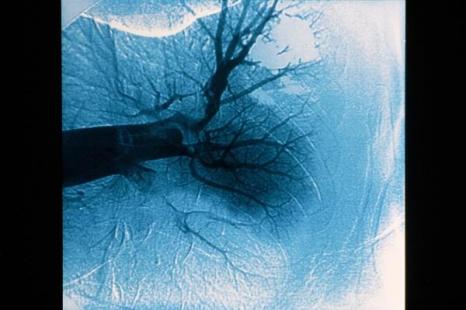

À partir de bases de données hospitalières, l'évolution épidémiologique de l'embolie pulmonaire a été retracée en Angleterre, entre 1998 et 2015 (Stephen Wort et al). 464 046 patients ont été hospitalisés avec ce diagnostic pendant cette période. L'incidence de l'embolie pulmonaire a plus que doublé, passant de 50,2/100 000 habitants/an en 1998, à 97,8/100 000 habitants/an en 2014. La mortalité globale à un mois du diagnostic d'embolie pulmonaire était de 15 %, et diminuait significativement sur la période de l'étude. De façon intéressante, l'incidence des complications hémorragiques augmentait sur la même période. Ces résultats sont vraisemblablement expliqués par l'utilisation croissante de l'angioscanner thoracique, qui permet de visualiser probablement beaucoup plus d'embolies pulmonaires. Quant à l'augmentation des complications hémorragiques enregistrées dans cette étude, même s'il s'agit d'analyses globales de bases de données, elle doit rappeler au praticien la nécessité d'évaluer cliniquement les signes évocateurs d'embolie pulmonaire… ainsi que le risque hémorragique !

Une seconde étude, présentée par Benoît Côté, s'est intéressée à l'impact pronostique de la dilatation du ventricule droit chez des malades avec une embolie pulmonaire à faible risque de complication. Les données de trois cohortes prospectives ont été regroupées. Les malades avec un score PESI simplifié égal à 0 (âge < 80 ans, absence d'insuffisance cardiorespiratoire ou de cancer, pouls < 110/min, pression artérielle systolique > 100 mmHg et SaO2 > 90 %) ont été inclus. Le rapport VD/VG était mesuré sur les angioscanners. 780 patients ont été inclus, et une dilatation du ventricule droit (VD/VG ≥ 0,9) était retrouvée chez 420 d'entre eux (54 %).

À 30 jours, une complication majeure, définie par un décès quelle que soit la cause, un état choc ou une récidive d'embolie pulmonaire, était survenue chez 6 patients (0,8 %). Il n'existait pas de différence concernant la survenue d'une complication à un mois, chez les patients avec ou sans dilatation du ventricule droit. Toutefois, le taux de complications était significativement plus important chez les malades qui avaient un ventricule droit très dilaté (VD/VG > 1,1). Les résultats de cette étude suggèrent que la dilatation du ventricule droit mesuré au scanner est relativement fréquente chez les malades à faible risque de complication mais que cette dilatation ventriculaire droite n'a pas d'impact pronostique évident. Néanmoins, il convient probablement d'être prudent les malades ayant le ventricule droit très dilaté (VD/VG >1,1) et de réaliser une échocardiographie avant de discuter une éventuelle prise en charge en ambulatoire.

Enfin, une troisième communication, présentée par Patrick Flood Page s'est intéressée à la fréquence de la dyspnée d'effort au décours d'un épisode d'embolie pulmonaire anatomiquement proximale. 127 malades ont été suivis. Parmi eux, 49 patients (48,5 %) rapportaient une limitation à l'effort plus importante qu'avant l'épisode d'embolie pulmonaire. Cette proportion augmentait à près de 75 % lorsqu'il y avait en plus une dilatation ventriculaire droite sur l'angioscanner. Parmi eux, 5 patients gardaient des séquelles d'embolie pulmonaire ou une hypertension pulmonaire post-embolique. Ces données soulignent l'importance de rechercher par l'interrogatoire une dyspnée d'effort au décours d'une embolie pulmonaire et d'en rechercher les causes possibles par les examens appropriés (radiographie thoracique, EFR, échocardiographie, scintigraphie pulmonaire...).